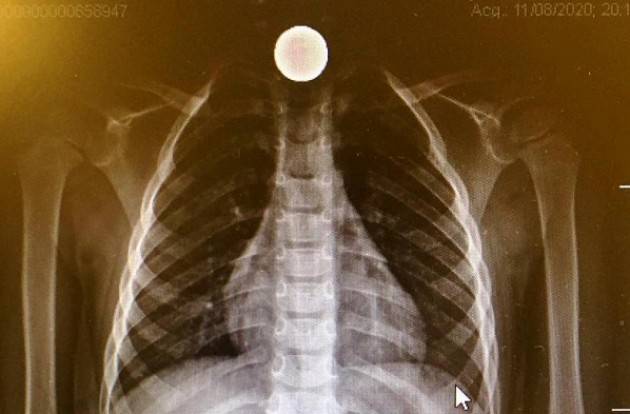

Durante la visita non emerge niente di particolarmente preoccupante, non vi erano segni di difficoltà respiratoria, in gola non si vede nulla. Quel sospetto, però, va assolutamente fugato. Per questo si procede subito con l’effettuazione di una lastra. Ed ecco che la moneta appare, nitida, “fra le tonsille e la laringe (uno spazio delicato di circa tre centimetri) – spiega Claudio Cavalli (Direttore UO Pediatria Aziendale). Era inserita a modi salvadanaio, dritta dritta, come si vede dall’immagine radiologica. Bisogna agire in fretta, abbiamo pensato, perché se si mette di traverso, possono insorgere complicanze, anche serie”.

“La vera sorpresa è stata scoprire che si trattava di una moneta da 20 centesimi – conclude Grassia. Dalla radiografia e dalle dimensioni pensavamo fossero due euro, in proporzione all’esofago di un bimbo quasi un disco volante. Se per gli adulti questa procedura endoscopica può ritenersi routine, non è così per i più piccoli”.

foto n. 1 ingestione moneta da 20 centesimi_radiografia bimbo 3 anni